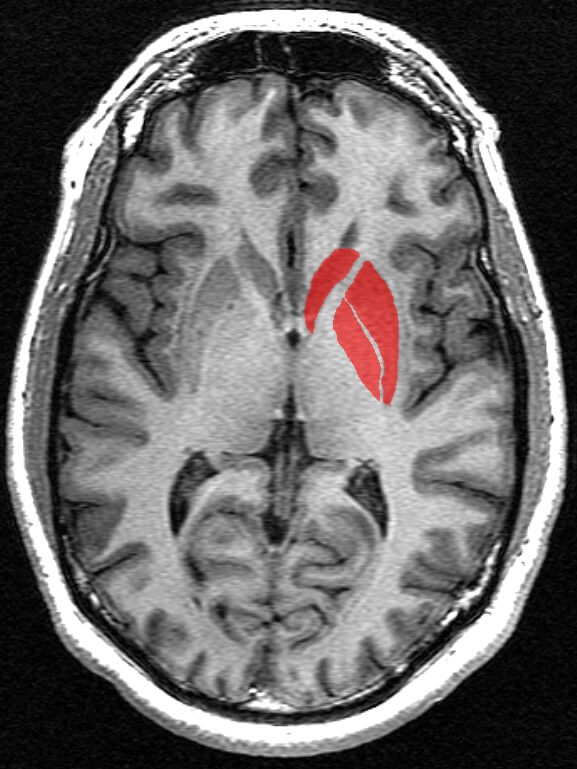

Núcleo putamen

El núcleo putamen es una estructura que se encuentra situada en el centro del cerebro. Concretamente, se halla justo al lado del núcleo caudado.

Resulta uno de los tres núcleos principales de los núcleos basales del cerebro, los cuales se encargan mayormente del control motor del cuerpo. Es la porción más externa de los núcleos basales y parece jugar también un papel importante en el condicionamiento operante.

Finalmente, las últimas investigaciones acerca de esta estructura cerebral la relacionan con el desarrollo de sentimientos. Específicamente, se postula que el núcleo putamen podría intervenir en la aparición de sentimientos de amor y odio.